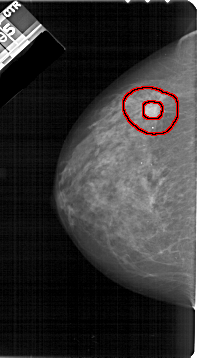

A_1211_1.RIGHT_CC

RIGHT_CC LINES 5176 PIXELS_PER_LINE 2686 BITS_PER_PIXEL 12 RESOLUTION 43.5 NON_OVERLAY